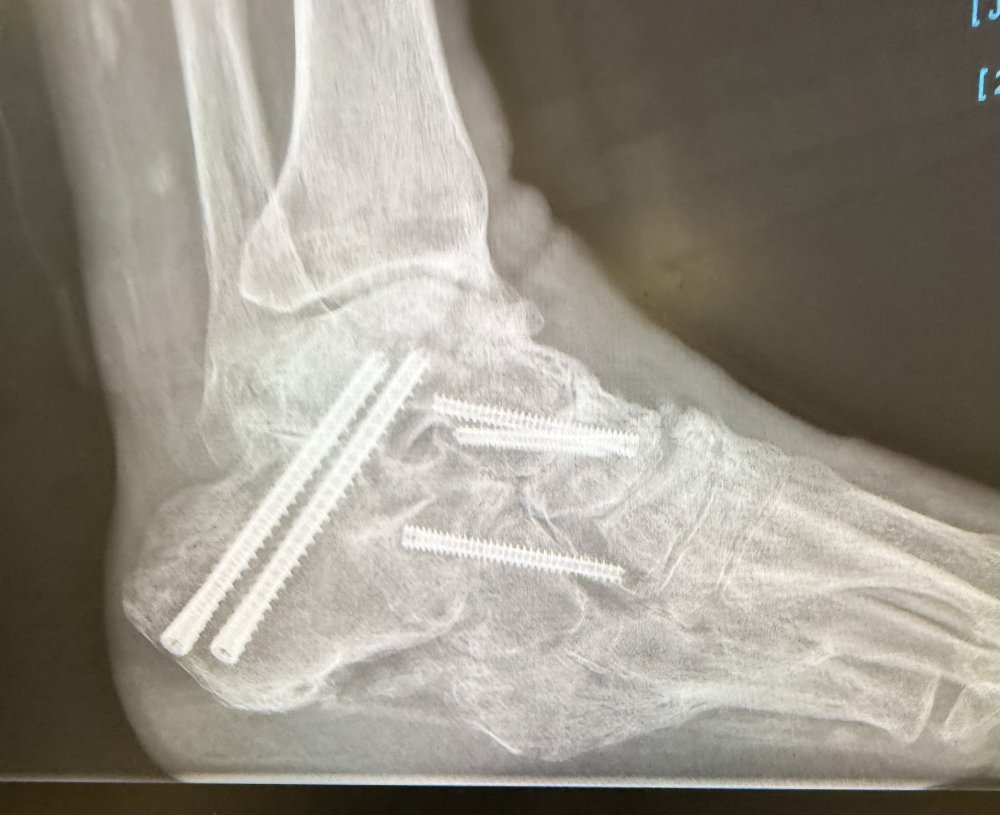

Ashley D Austin Posted October 3 Posted October 3 (edited) I have had foot surgery and the bone in my foot is now permanently higher than it was before and it is very painful to wear any type of closed leather shoe or boot. Soft hiking boots and sneakers are much more comfortable. This spring, I attended a state match and was told I had to wear "cowboy boots". I looked around and saw men wearing leather and soft lace-up shooting boots (which are not cowboy boots), lace-up soft hiking boots, sneakers (tennis shoes), and one that was wearing black socks and black sandals. I am not complaining about being singled out, but I would like a definitive answer from SASS about what the official determination is on footwear for age-based categories? Edited October 3 by Ashley D Austin 2 Quote